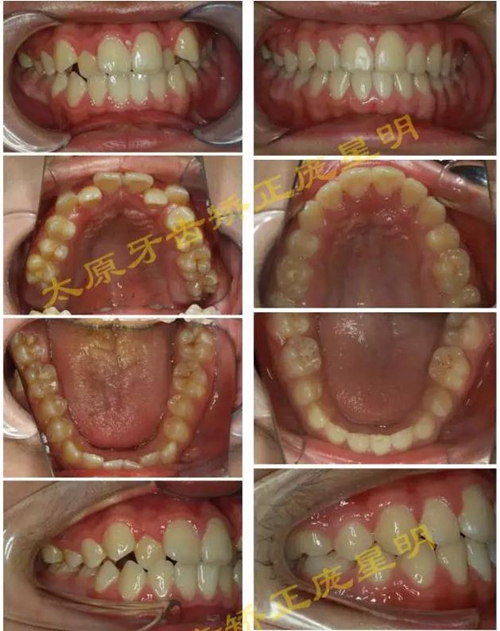

1500865770_445373.jpg1500865976_358577.jpg

此病例主要考慮的是擁擠度,磨牙及尖牙關(guān)系,前牙覆合覆蓋,生長潛力和智齒。